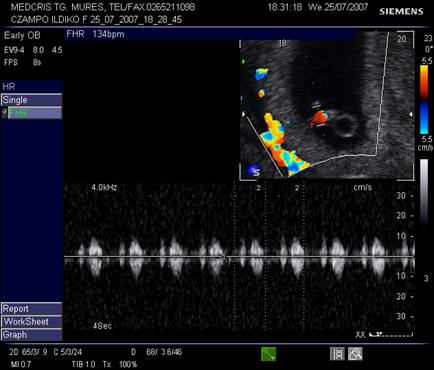

Fig nr. 13. Embrion cu activitate cardiaca, examen Doppler pulsat si Color Flow Map, ritm cardiac de 134 batai pe minut